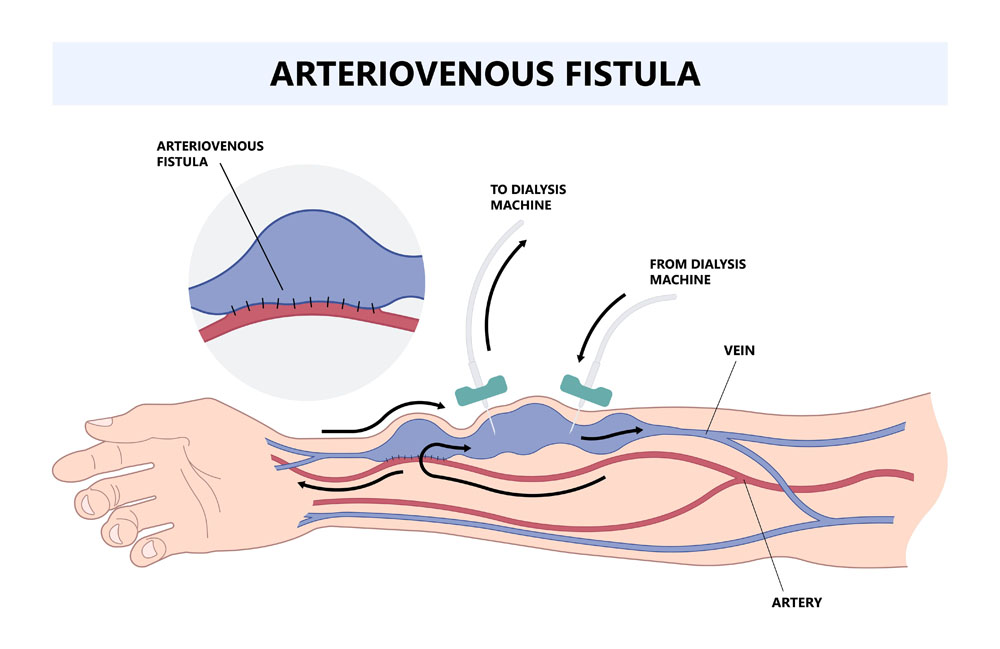

Ein Dialyseshunt, auch bekannt als arteriovenöser (AV) Shunt, ist eine lebenswichtige chirurgische Verbindung zwischen einer Arterie und einer Vene, die speziell für Patienten geschaffen wird, die eine regelmäßige Hämodialysebehandlung benötigen. Diese künstliche Verbindung wird meist im Arm angelegt und erleichtert den wiederholten Zugang zum Blutkreislauf für die Dialyse, eine Behandlung, die notwendig ist, wenn die Nieren nicht mehr in der Lage sind, das Blut effektiv zu filtern.

- Arteriovenöse Fistel (AVF): Eine direkte Verbindung zwischen einer Arterie und einer Vene, vorzugsweise im Unterarm, die einen robusten und langlebigen Zugang für die Dialyse bietet.

Die erfolgreiche Anlage eines Dialyseshunts ist ein entscheidender Schritt in der Vorbereitung auf eine regelmäßige Hämodialysebehandlung für Patienten mit fortgeschrittenem Nierenversagen. Ein neu angelegter Shunt benötigt in der Regel bis zu 6 Wochen Zeit, um sich zu "reifen" – das heißt, bis er vollständig verheilt ist und die Venen ausreichend erweitert sind, um den hohen Blutfluss, der für die Dialyse erforderlich ist, zu unterstützen.